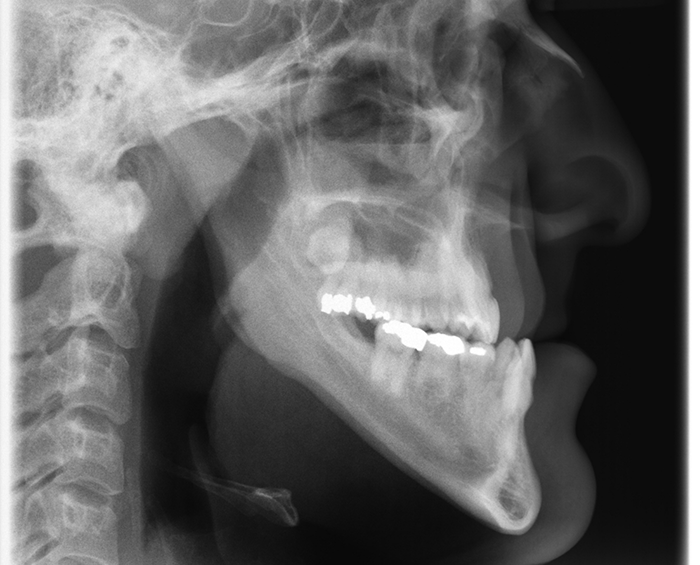

Surgical Case

Patient presented with a class III profile, underbite. The patient underwent orthodontic and surgical treatment. Facial profile showed significant improvement.